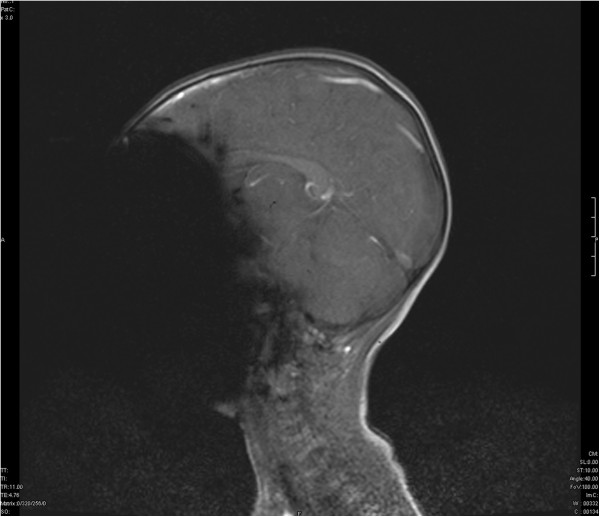

Interestingly, a second MRI showed that there was still some ionic material left behind in the mucosa - the shaded areas corresponding to the right nasal cavity. The symptoms quickly resolved with antibiotics and the child made a good recovery.